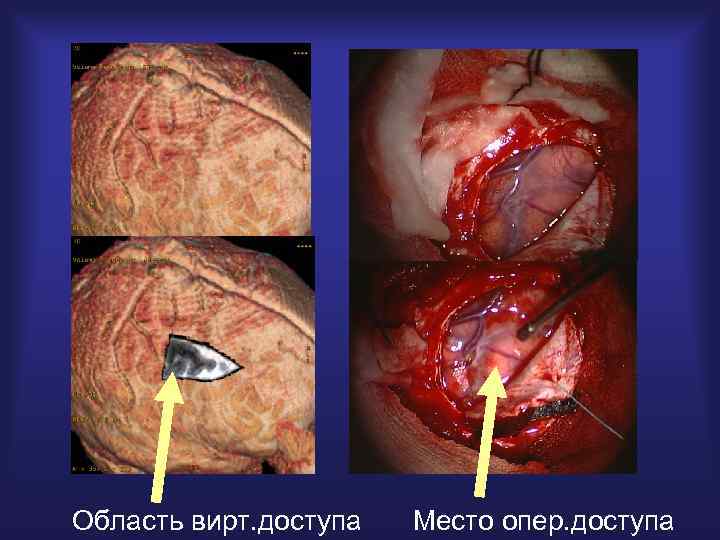

Виртуальное моделирование операции

Область вирт. доступа Место опер. доступа